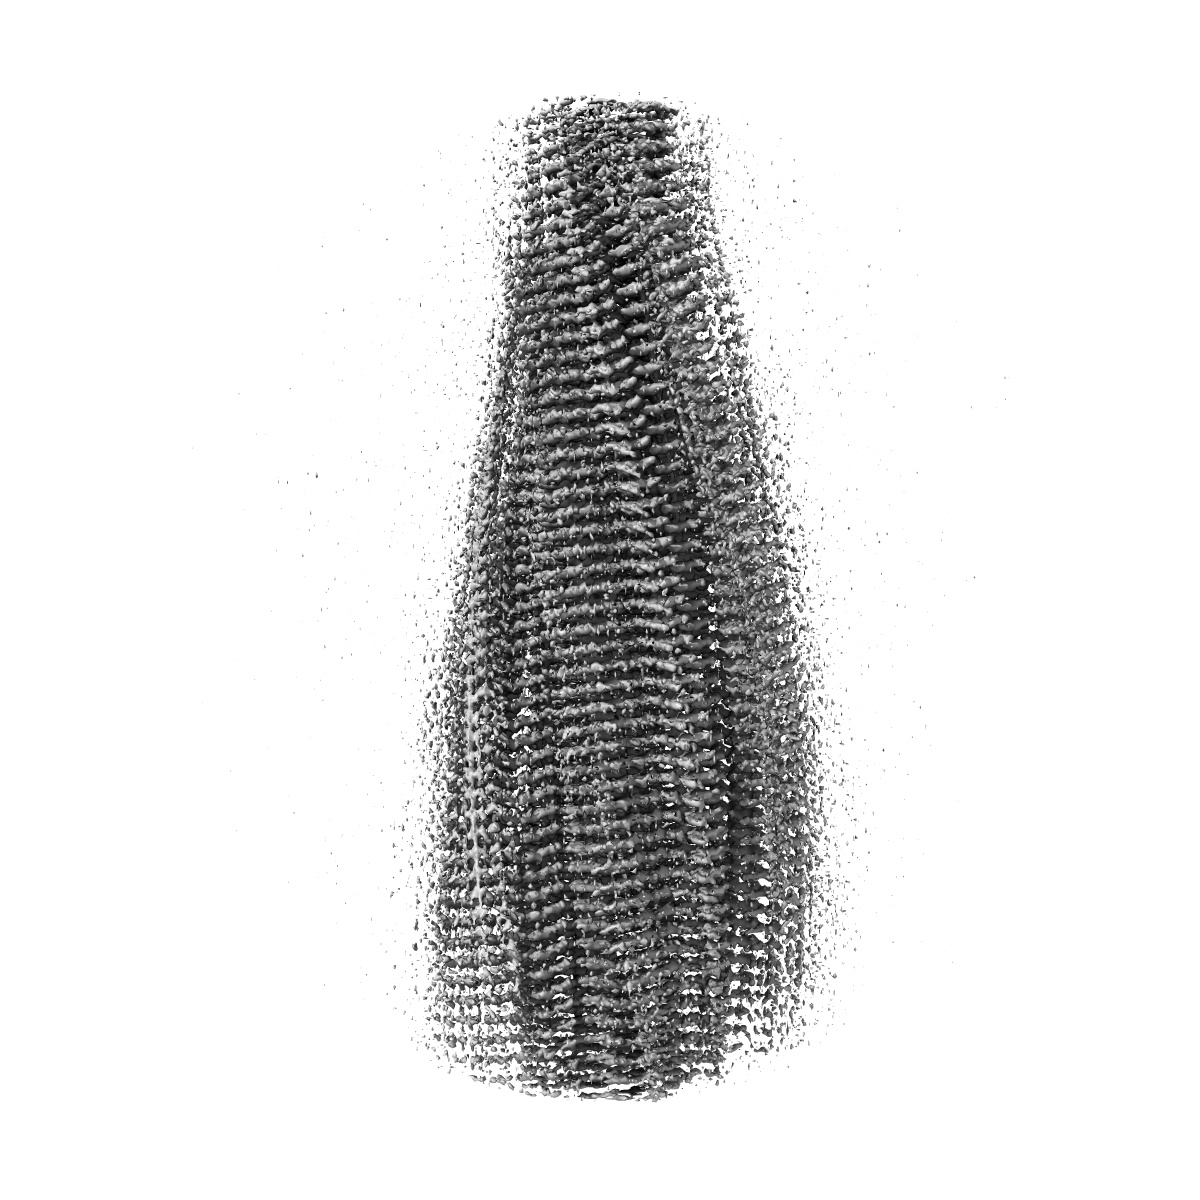

CryoEM Structure of 40-Residue Arctic (E22G) Beta-Amyloid Fibril Derived by Co-Analysis with Solid-State NMR | E22G Abeta40

Helical reconstruction2.5 Å

Sample: Amyloid Fibril of 40-Residue Beta-Amyloid with Arctic (E22G) mutation

E22G A beta 40 fibril structure and kinetics illuminate how A beta 40 rather than A beta 42 triggers familial Alzheimer's.